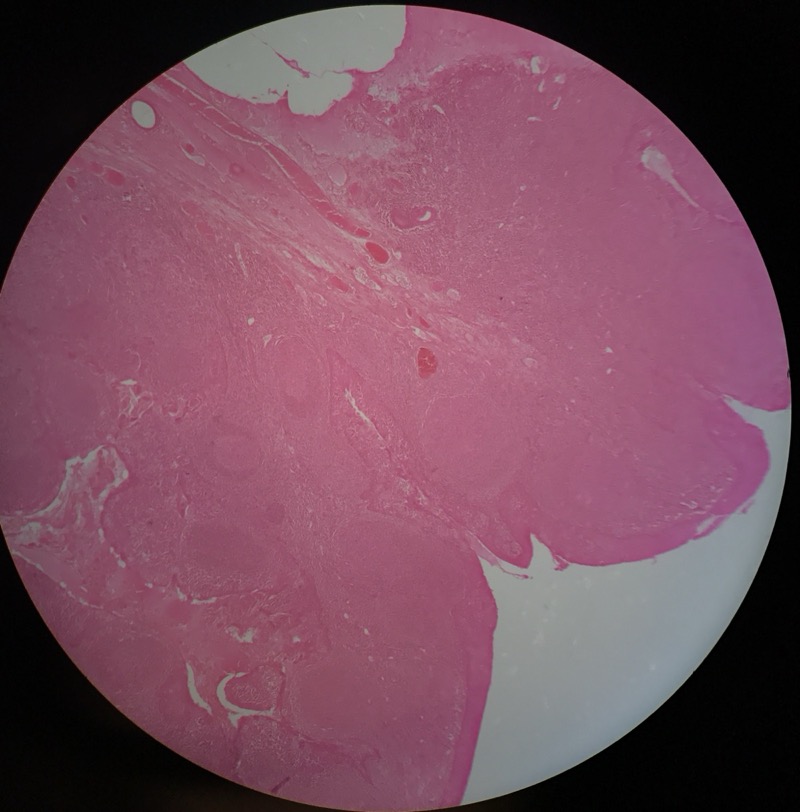

| 3:2:1 | Hjärtmuskel | Hjärta | ![]() |